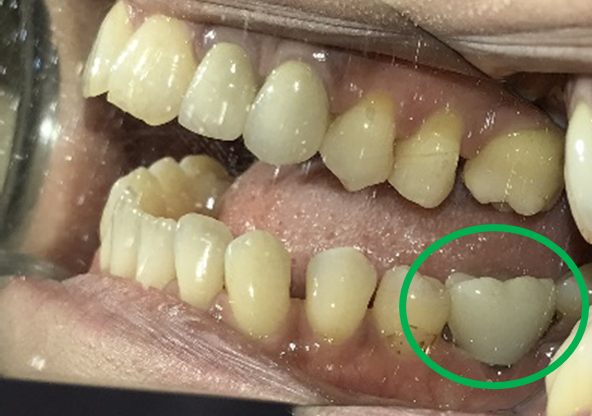

女性Sさん 60代(インプラント)

主訴

左下が腫れていて、噛むと痛い。

治療内容

左下ブリッジの支台になっている大臼歯が、歯根の破折を起こしていましたので、抜歯しました。奥歯3本欠損のところに、2本インプラントを埋入しました。

所感

奥歯3本歯のないところを補う方法は、インプラント、あるいは取り外しの部分入れ歯、という2つの方法があります。部分入れ歯は支台になっている歯に負担がかかるため、問題が起きた時には、支台になっている歯がダメになり、更に抜歯になる可能性が大きいです。最初は3本の欠損から、4本、5本と歯がないところが拡大してしまいます。また、義歯は異物感が大きく慣れるのが大変で、上下自分の歯どうしで噛む感覚と同じようには噛むことができません。

インプラントは、単独で植立し他の歯に負担がかからなく、自分の歯と同じような感覚で食事が出来ます。患者さんは、インプラント治療を選択されました。治療後、「約半年と時間がかかり、緊張の連続でしたが、丁寧に治療してもらいありがとうございました。今日から両側の歯で噛めるので、安心しました。」と、とても喜んでくださいました。

この症例は、3DナビゲーションシステムのX-ガイドを使って埋入しました。X-ガイドは骨の中の神経や血管の位置をリアルタイムに確認しながら手術が実行できるため、より安全で精度の高いインプラント埋入ができます。

インプラント2本:¥363,000×2本=¥726,000(税込)

ポンティック1本(インプラント間をつなぐ部分):¥115,500(税込)

合計:¥841,500(税込)